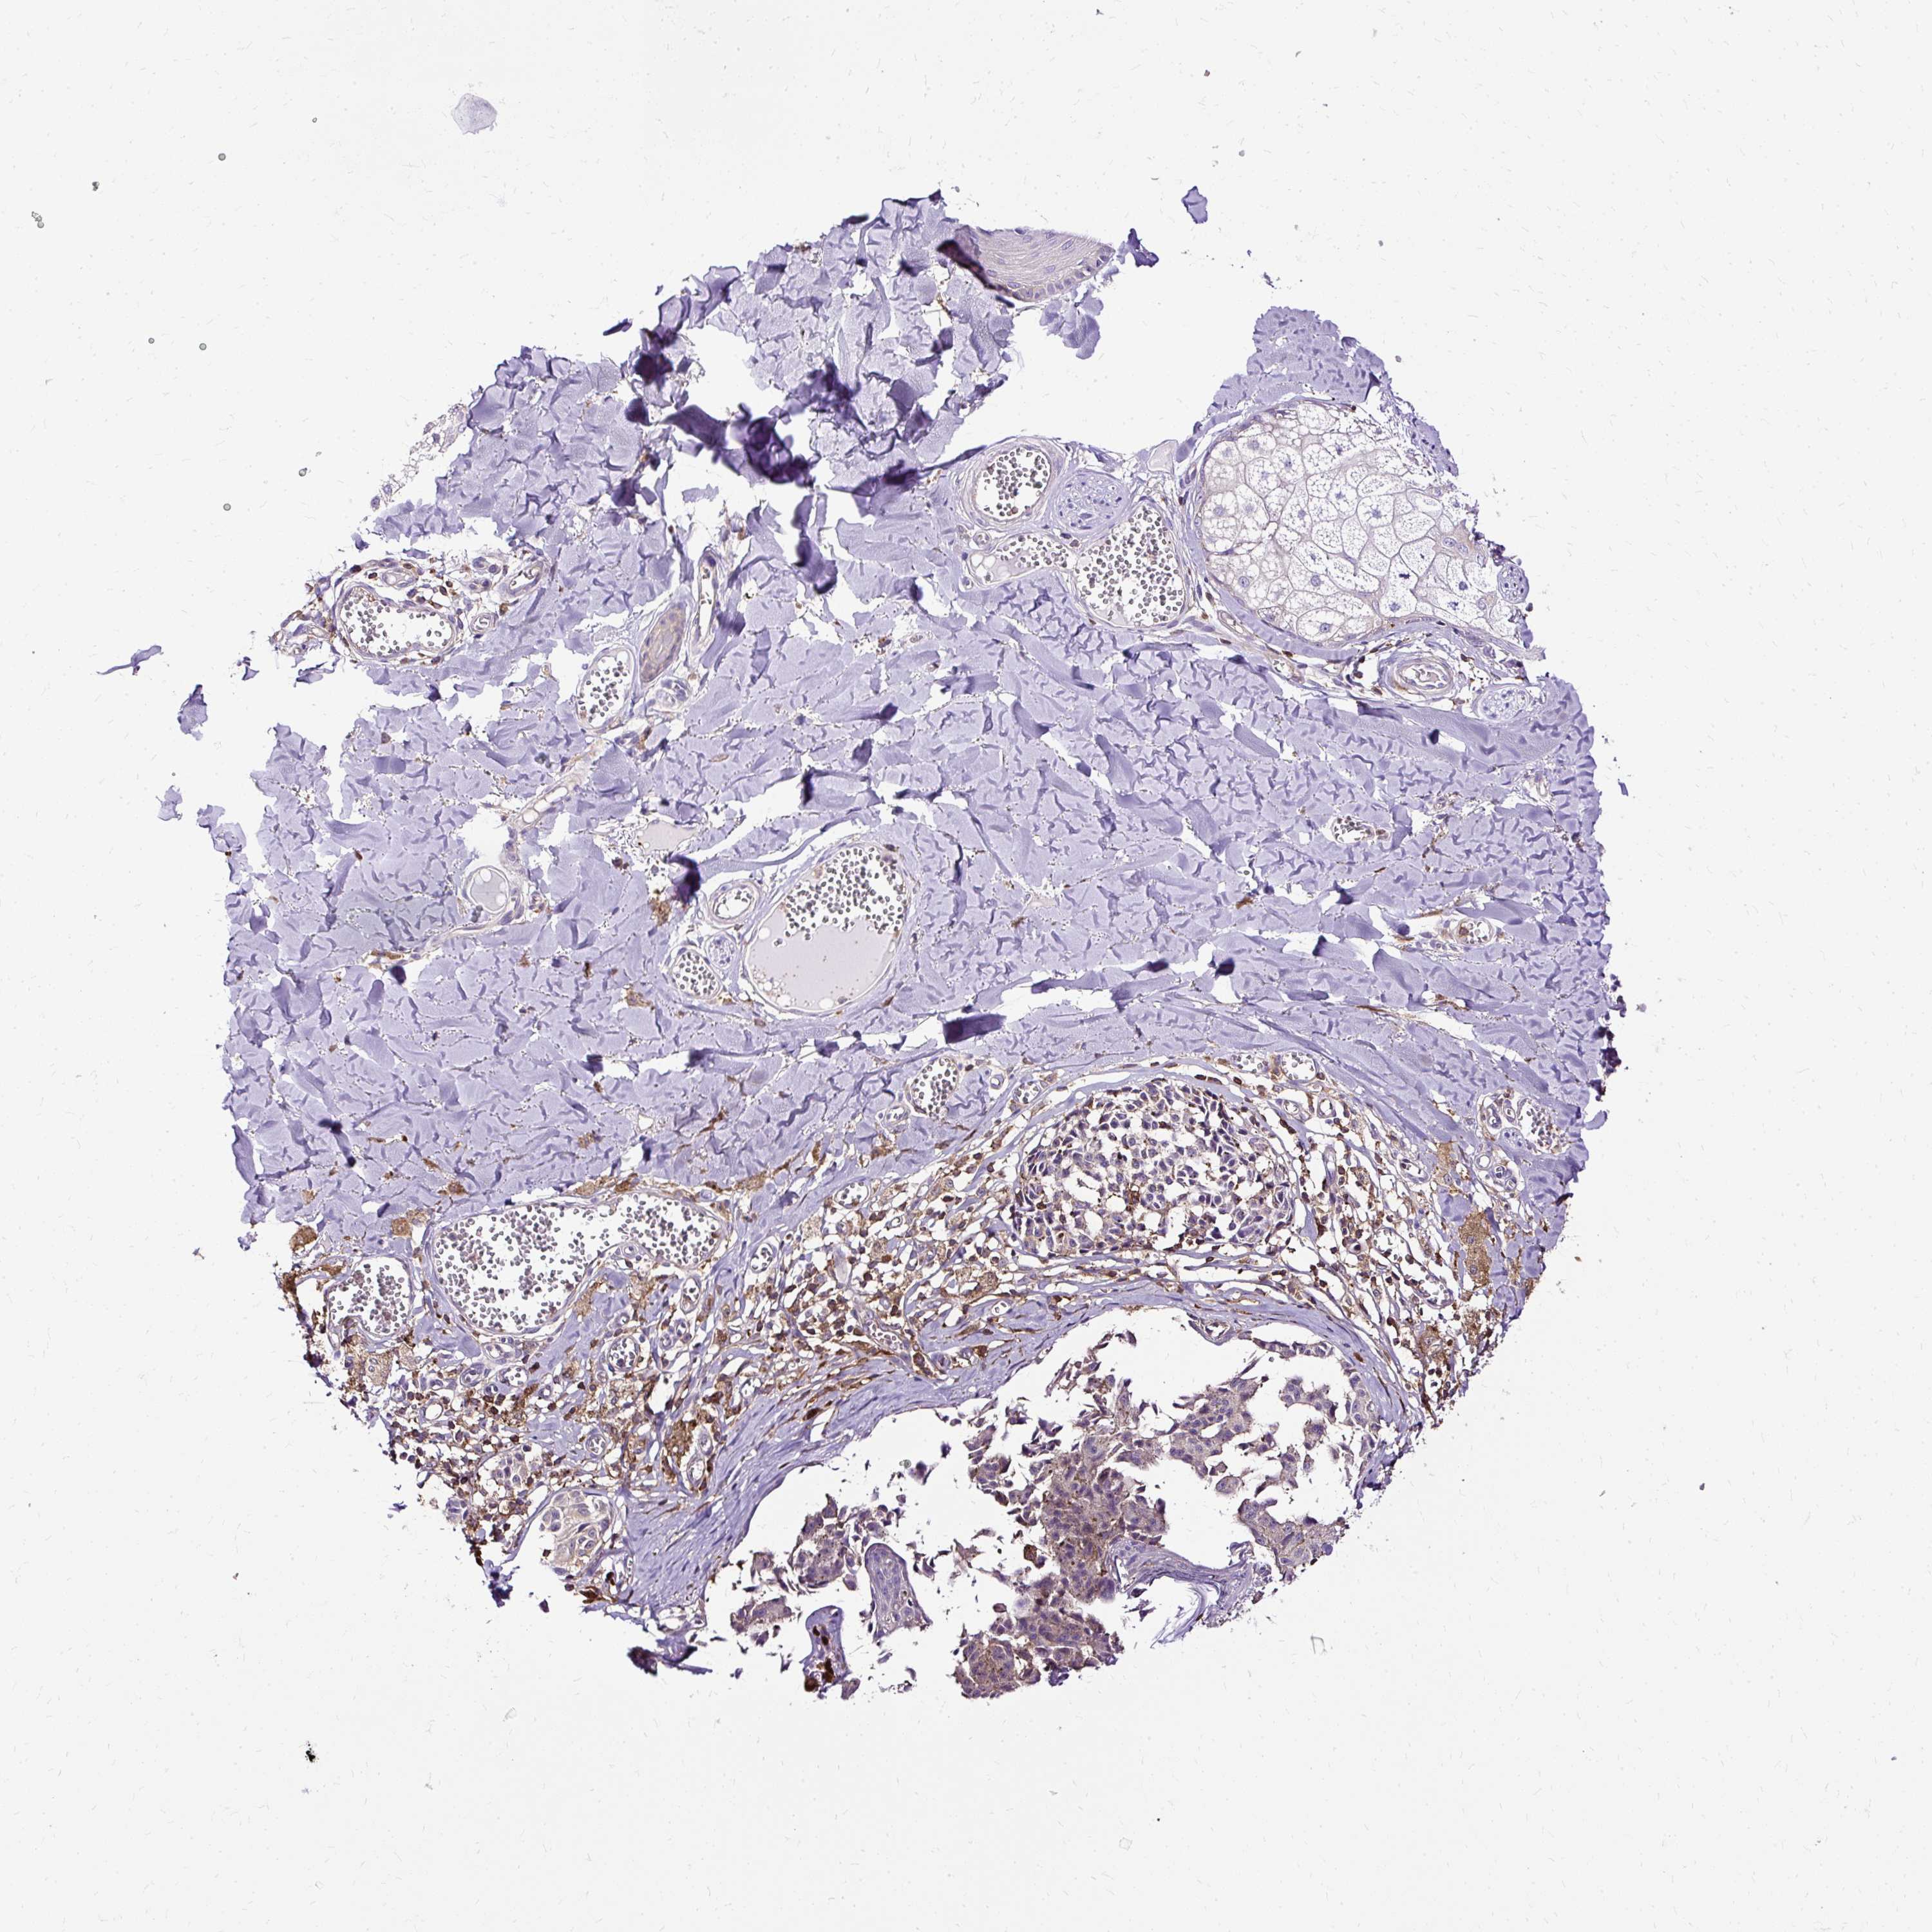

MELANOMA - Protein expressioni

A mouse-over function shows sample information and annotation data. Click on an image to view it in a full screen mode. Samples can be filtered based on level of antibody staining by selecting one or several of the following categories: high, medium, low and not detected. The assay and annotation is described here.

Note that samples used for immunohistochemistry by the Human Protein Atlas do not correspond to samples in the TCGA dataset.

Antibody stainingi

Antibody staining in the annotated cell types in the current human tissue is reported as not detected, low, medium, or high, based on conventional immunohistochemistry profiling in selected tissues. This score is based on the combination of the staining intensity and fraction of stained cells.

Each image is clickable and will lead to virtual microscopy that enables deeper exploration of all samples and also displays staining intensity scores, fraction scores and subcellular localization as well as patient and tissue information for each sample.

Antibody HPA053874

Staining

High

Medium

Low

Not detected

Intensity

Strong

Moderate

Weak

Negative

Quantity

>75%

75%-25%

<25%

None

Location

Nuclear

Cytoplasmic/membranous

Cytoplasmic/membranous,nuclear

Malignant melanoma, NOS

Malignant melanoma, Metastatic site